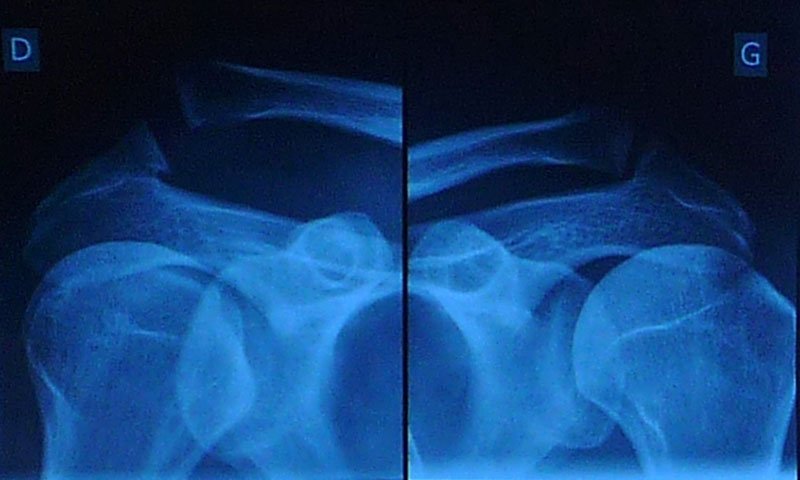

AC syndesmolisis dex. gradus III. Izpahnjena ključnica po domače, kar se sliši precej pomirjujoče. Žal to vključuje tudi tri strgane vezi in operacijo, po kateri sem zaradi železja malo težji. Po mesecu dni (19.8.) je rama lepo gibljiva do 90° in dokler me čez tri tedne ne olajšajo za železnino, roke višje sploh ne smem dvigniti, potem pa...